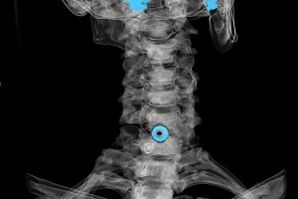

Diagnosis is based on characteristic symptoms and using:

- X-rays.This approach is ineffective, especially in the final stages of osteochondrosis development.

- MRI (magnetic resonance imaging) of the cervical spine.A method that allows you to see the bone structure, the herniated disc, its size and direction of development.

- Computed tomography.This is a less effective solution than an MRI because it is difficult to determine the presence and size of the hernia.